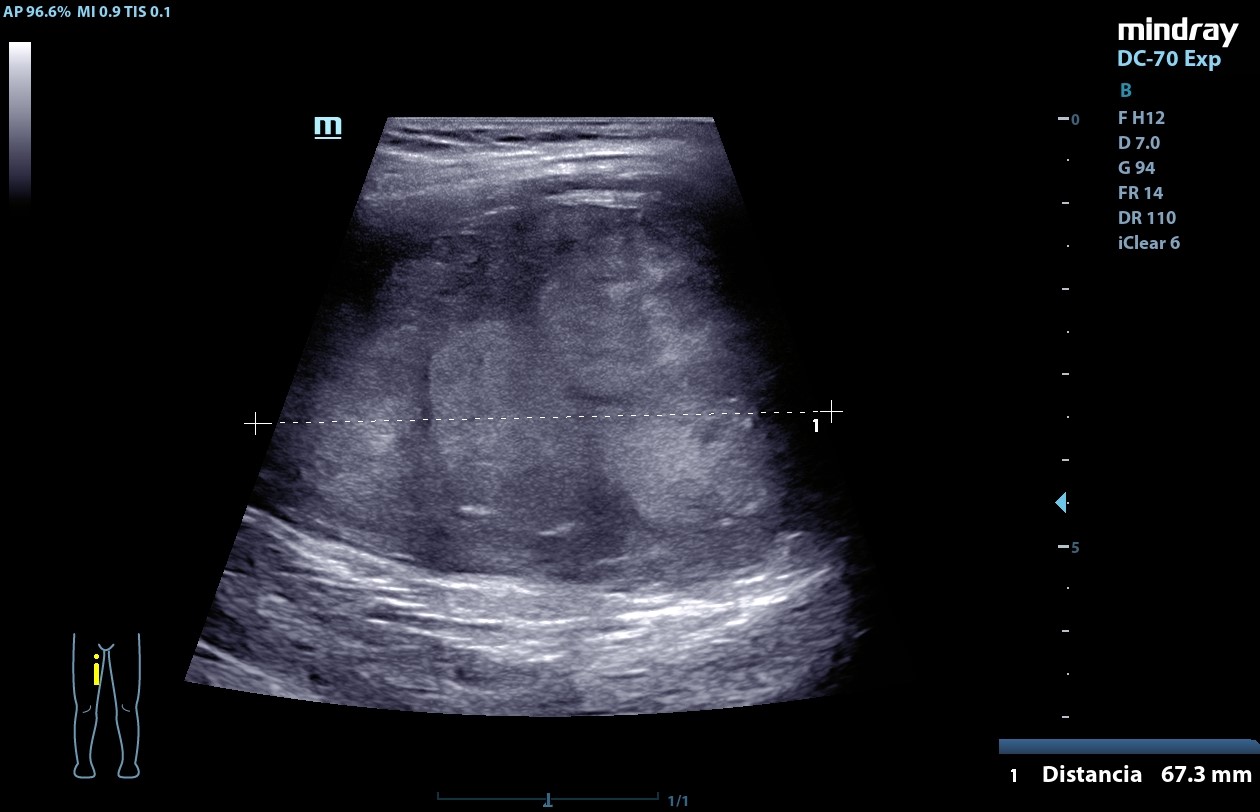

Ecografía POCUS (20/09/24): masa heterogénea de centro hiperecogénico, de bordes bien definidos, Doppler negativa de aproximadamente 52,3 mm x 37,4 mm x 67,3 mm compatible con neurofibroma plexiforme.